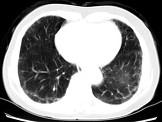

问题 女,35岁,咳嗽,咳痰,发热3月余,胸部CT如图,最可能的诊断为 ( )

选项 A.类风湿肺炎 B.红斑狼疮性肺炎 C.间质性肺炎 D.肺结节病 E.肺部感染

答案 C